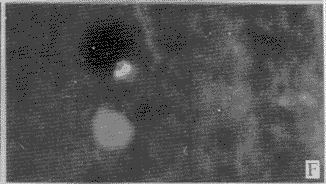

2.2 DM对分离脑细胞DNA的损伤:正常情况下胞核染色近似圆形,边缘清楚,染色均匀(图2-A)。当细胞发生凋亡时,细胞核染色体凝集成块,着色较重,且细胞缩小,因核膜仍然存在,故DNA虽然碎裂,但仍集中在一起。图2-B显示细胞核碎裂成3块,图2-C显示细胞核碎裂成多块;图2-D显示染色质开始浓缩,边缘不整齐;图2-E显示染色质浓缩,靠近核膜,从而形成环状DNA;图2-F~H可见凋亡小体的形成过程,染色质浓缩,边缘不整,图9可见凋亡小体从细胞核分裂出来。

A 正常形态的DNA,×200 (孵育15分钟)

B DNA细胞核碎裂为3块,×400 (孵育60分钟)

C 细胞核碎裂为多部分,但尚未形成凋亡小体,×400 (孵育30分钟)

D 凋亡细胞染色体凝集成块,边缘不整齐,×200 (孵育30分钟)

E 染色质靠近核膜,形成环状DNA,×400 (孵育90分钟)

F 染色质浓缩,可见凋亡小体的形成过程,×200 (孵育60分钟)

G 染色质浓缩,可见凋亡小体的形成过程,×400 (孵育120分钟)

H 凋亡小体从细胞核分裂出来,×200 (孵育120分钟)

图2 DM对分离神经细胞DNA的损伤(AO染色)A DNA in normal state,×200(incubated 15 min)

B DNA broke into three pieces,×400(incubated 60 min)

C DNA broke into many pieces,×400(incubated 30 min)

D Early stage of apoptotic cells,×200(incubated 30 min)

E A ring-like shape DNA,×400(incubated 90 min)

F Early stage of apoptotic cells, ×200(incubated 60 min)

, 百拇医药

G Early stage of apoptotic cells, ×400(incubated 120 min)

H Apoptotic body separated from nuclear, ×200(incubated 120 min)

Figure 2 Damage of DM on the DNA in rat dissociated neural cells(Stained by AO)